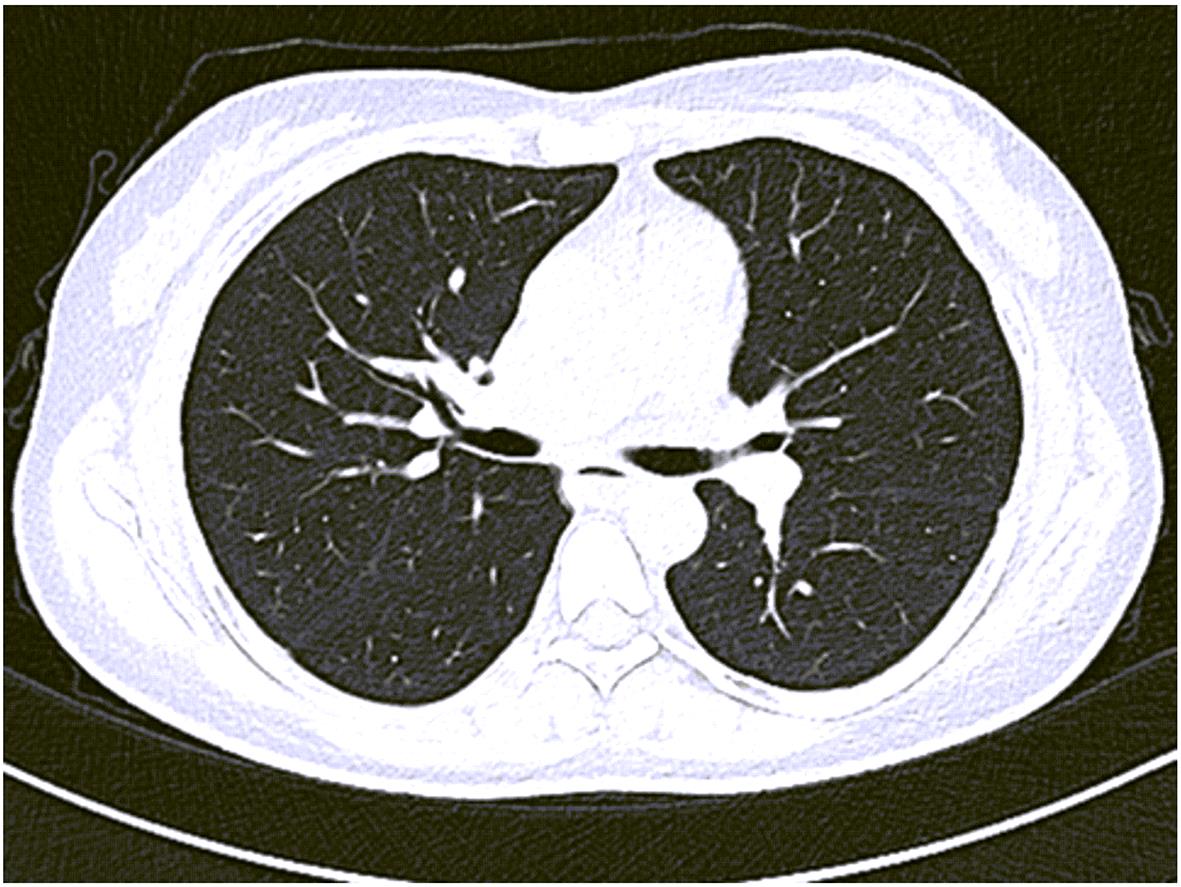

胰腺内副脾误诊2例报告

2024, 40(2): 365-368. DOI: 10.12449/JCH240223

摘要(1364) HTML (331) PDF (1188KB)(157)

摘要:

副脾是指正常脾脏以外存在的,与主脾结构相似,有一定功能的脾脏组织,其中完全被胰腺包裹的胰腺内副脾(IPAS)发生率仅为2%,因其临床症状不典型,影像学特征与胰腺神经内分泌肿瘤、胰腺实性假乳头状瘤以及其他胰腺占位性病变较为相似,临床上容易误诊。本文报道了2例分别被误诊为胰腺神经内分泌肿瘤和胰腺实性假乳头状瘤的IPAS患者,并分析误诊原因,总结诊疗经验,以期提升临床对IPAS明确鉴别诊断的认识。